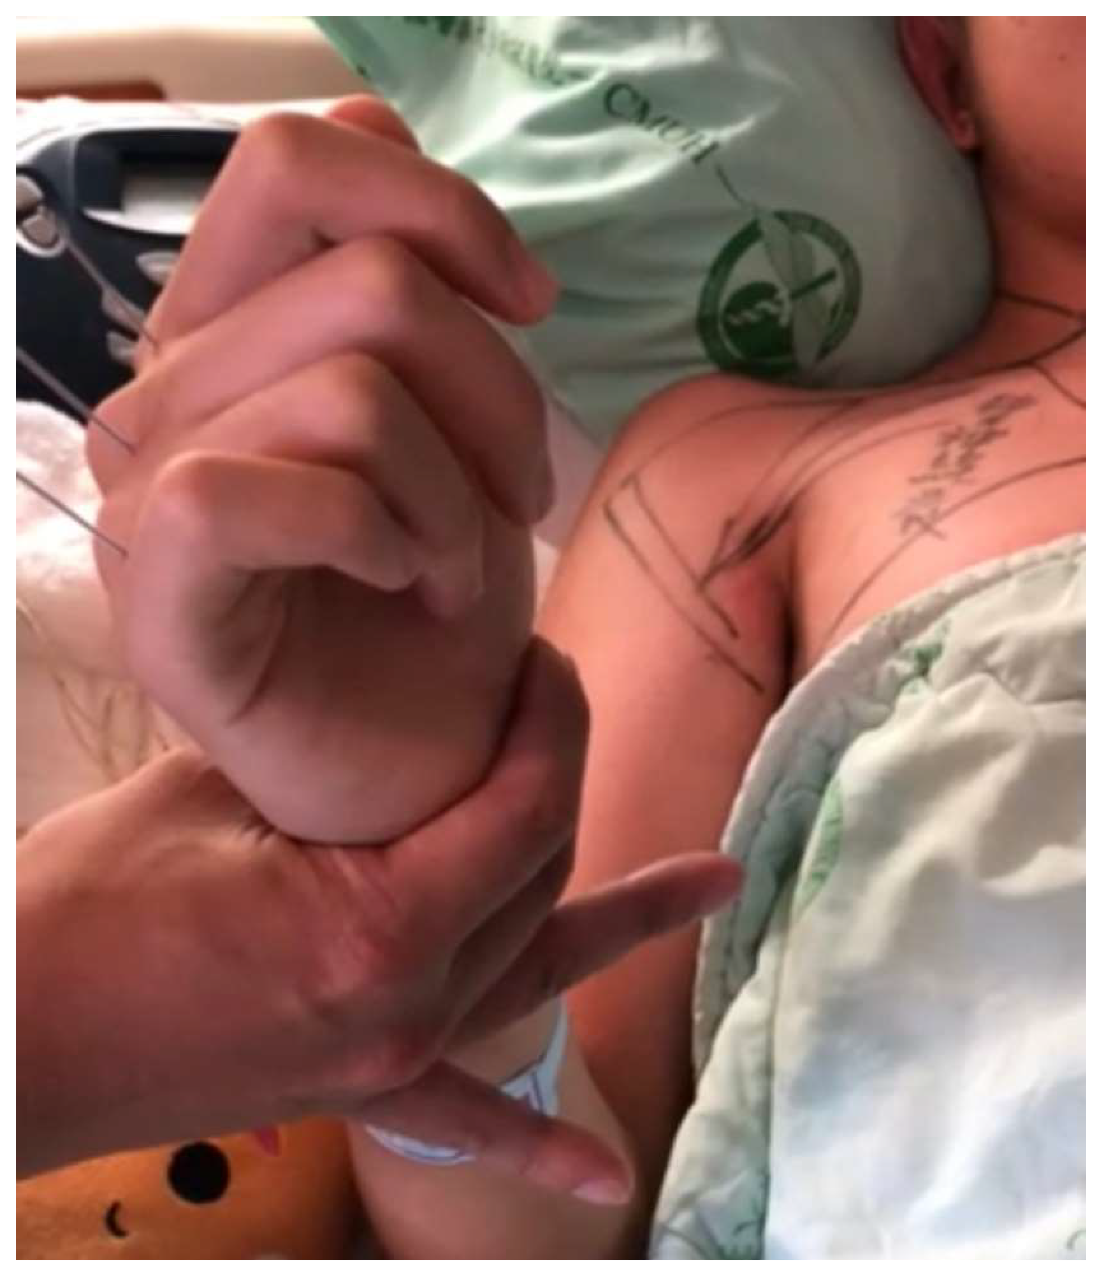

2.4. Surgical Procedure and Postoperative Care